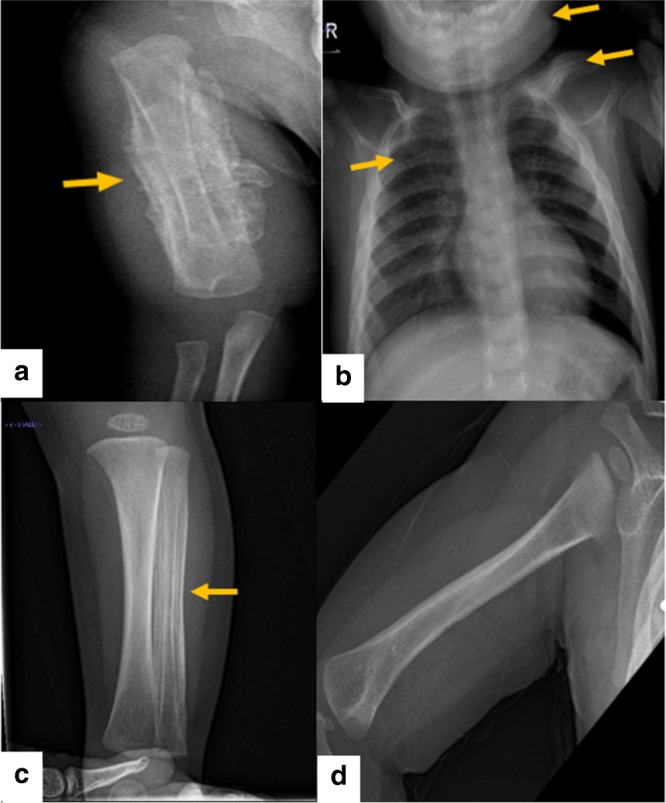

對右臂進行 X 光檢查,顯示沿右肱骨的整個骨干骨膜反應(yīng)旺盛(圖 1a)。 進一步評估包括 X 線骨骼檢查,顯示一側(cè)肩胛骨、一根腓骨、下頜骨和許多肋骨有明顯的骨膜反應(yīng)(圖 1b)。 根據(jù)臨床和放射學檢查結(jié)果,診斷為 ICH。 盡管德托尼-卡菲病可能具有短暫性,但開始使用吲哚美辛(每天 5mg/kg)治療,并且病變在幾個月內(nèi)有效消失,正如后續(xù)放射學檢查所證明的那樣(圖 1c)。 經(jīng)過 1 年的隨訪,患者有效康復,沒有骨骼畸形和/或升高的炎癥標志物。 他仍在服用低劑量的消炎痛(每天 1mg/kg)。

患者的射線照相檢查。 a 沿右肱骨整個軸的骨膜反應(yīng)。 b 沿左鎖骨、肋骨和下頜骨的骨膜反應(yīng)。 c 沿腓骨的骨膜反應(yīng)。 d 肱骨骨膜有效消退